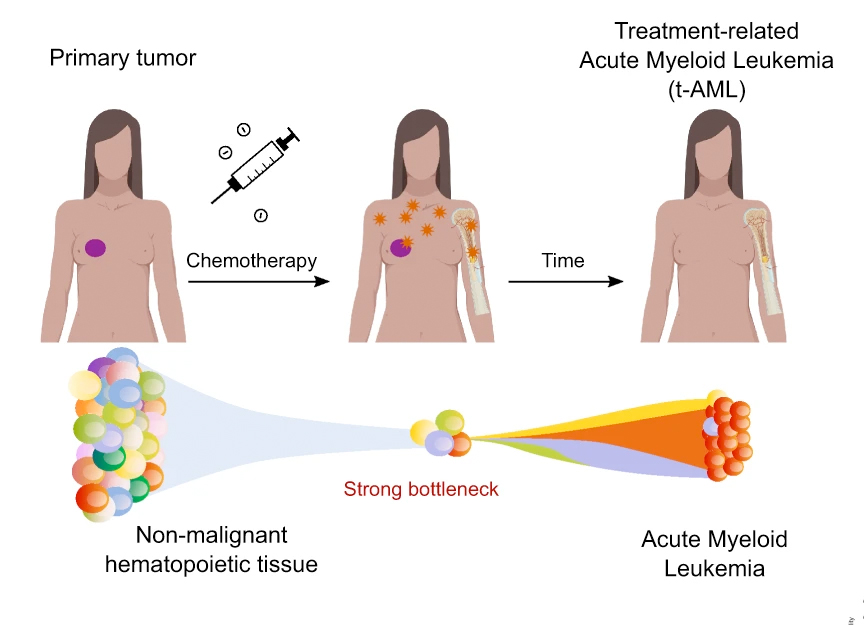

由ICREA研究员Núria López-Bigas领导的IRB巴塞罗那生物医学基因组实验室的研究人员,已经确定了铂基化疗在急性髓系白血病(AML)病例中留下的“足迹”(以DNA突变的形式),这些病例与之前对实体肿瘤的化疗治疗有关。这项研究发表在《自然通讯》杂志上。(The evolution of hematopoietic cells under cancer therapy)